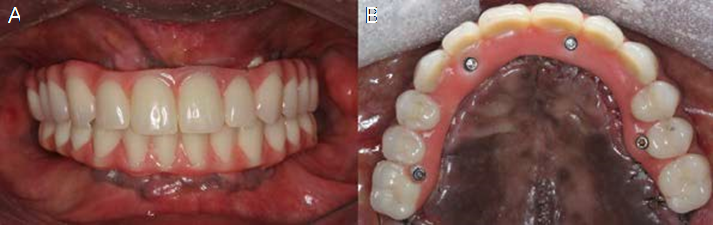

Forty-eight hours thereafter, the teeth were tried in, fixed with wax to the metal bar and on the third day the final prosthesis was inserted, according to the passive fit technique. Occlusal adjustments were performed, relieving excessive contact in excursive movements during the osseointegration period, but keeping the prosthesis in occlusion (Figure 4.A, Figure 4.B and Figure 5).

The patient returned with 14 days post-surgery to remove the suture and assess the clinical and radiographic condition of the rehabilitation. After 30 days and 6 months, success of implants and rehabilitation, favorable remodeling of the peri-implant tissues and satisfactory aesthetic and functional conditions were observed (Figure 6 and Figure 7).